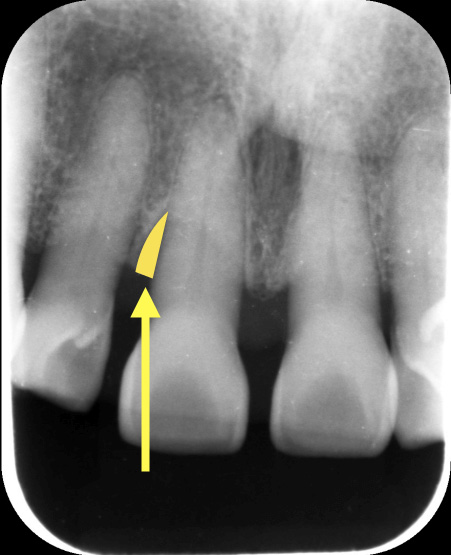

図1

黄色矢印部分は歯周ポケットが局所的に深くなっています。このようなポケットには細菌がたくさんいるために、放置すると、歯周病がどんどん進行し、歯が抜ける原因となります。